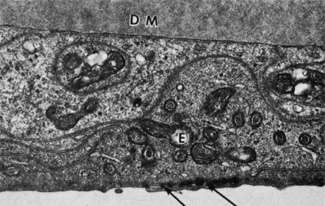

normal cornea. Arch Ophthalmol 100:1942, 1982 87. Bourne WM, Johnson DH, Campbell RJ: The ultrastructure of Descemet's membrane. III. Fuchs' dystrophy. Arch Ophthalmol 100:1952, 1982 88. Binder PS, Rock ME, Coalwell Schmidt K, et al: High-voltage electron microscopy of normal human cornea. Invest Ophthalmol Vis Sci 32:2234, 1991 89. Tamura Y, Konomi H, Sawada H, et al: Tissue distribution of type VIII collagen in human adult and fetal eyes. Invest Ophthalmol Vis Sci 32:2636, 1991 90. Klyce SD, Beuerman RW: Structure and function of the cornea. In Kaufman HE, Barron BA, McDonald MB, Waltman SR (eds): The Cornea. New York: Churchill Livingstone, 1988:3–54. 91. Williams K, Watsky M: Gap junctional communication in the human corneal endothelium and epithelium. Curr Eye Res 25:29, 2002 92. Waring GO, Bourne WM, Edelhauser HF, et al: The corneal endothelium: Normal and pathological structure and function. Ophthalmology 89:531, 1982 93. Kreutziger GO: Lateral membrane morphology and gap junction structure in rabbit corneal

endothelium. Exp Eye Res 23:285, 1976 94. Amann J, Holley GP, Lee SB, et al: Increased endothelial cell density in the paracentral and peripheral regions